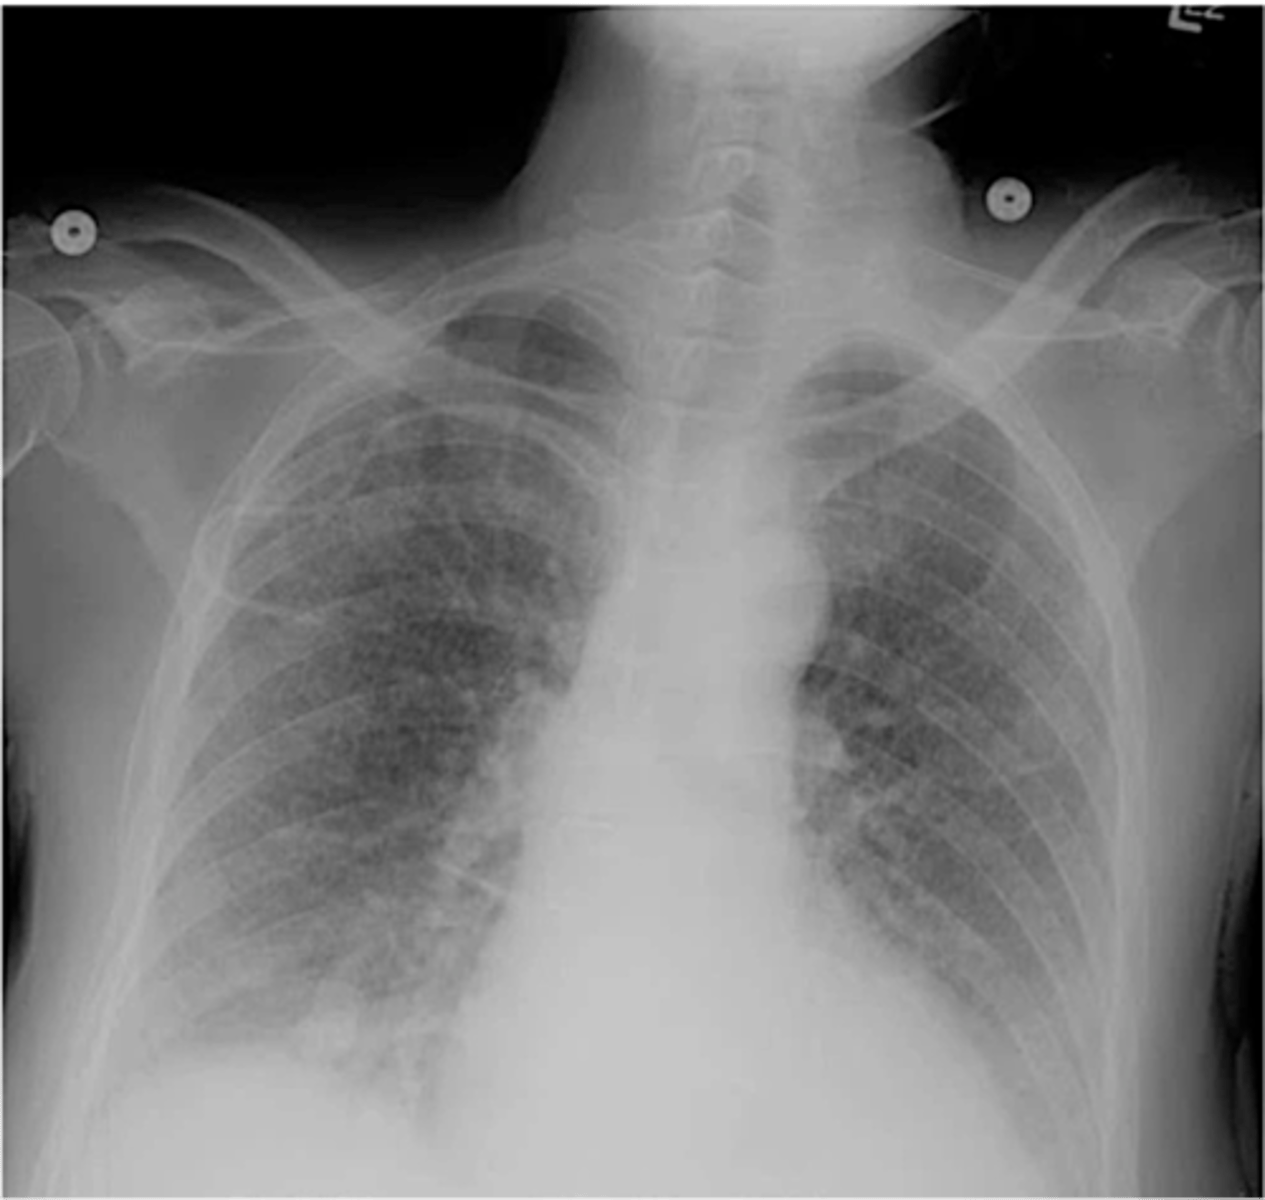

hyperinflation and flattening of the diaphragm

How does COPD appear on an XR